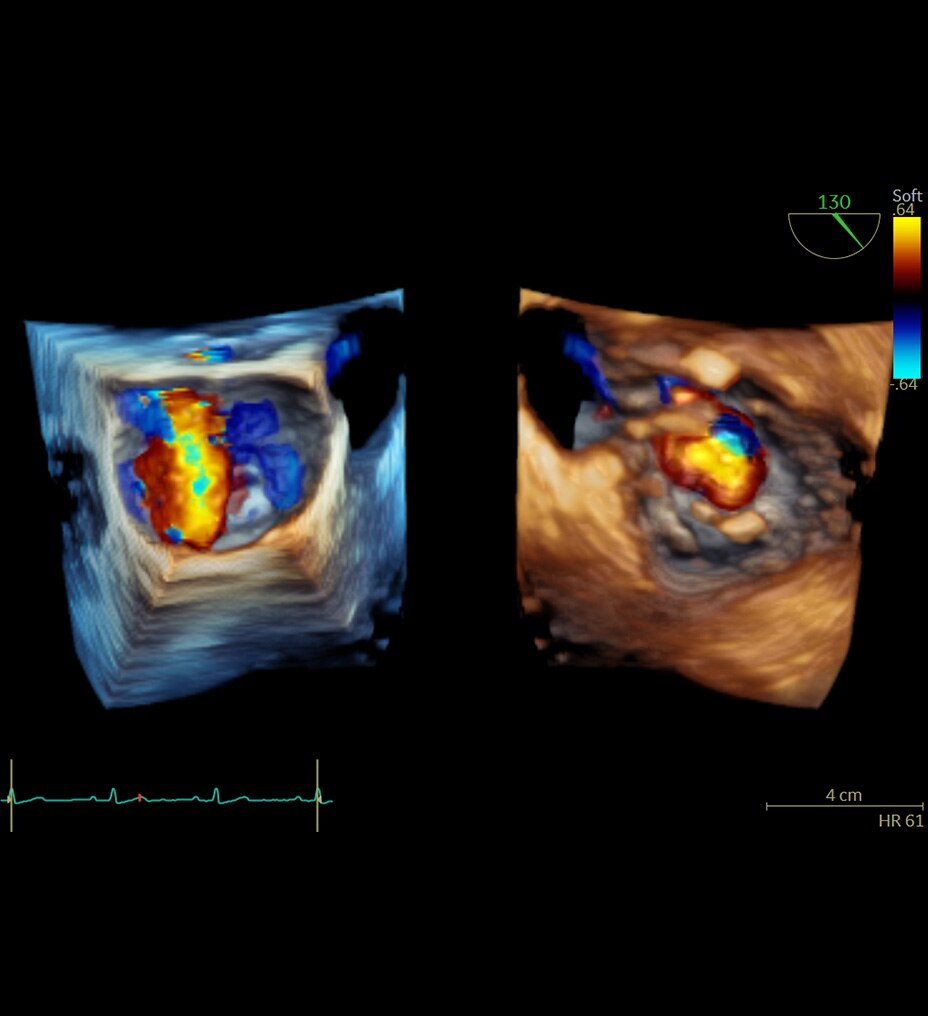

Flow Profiles

Go with the flow